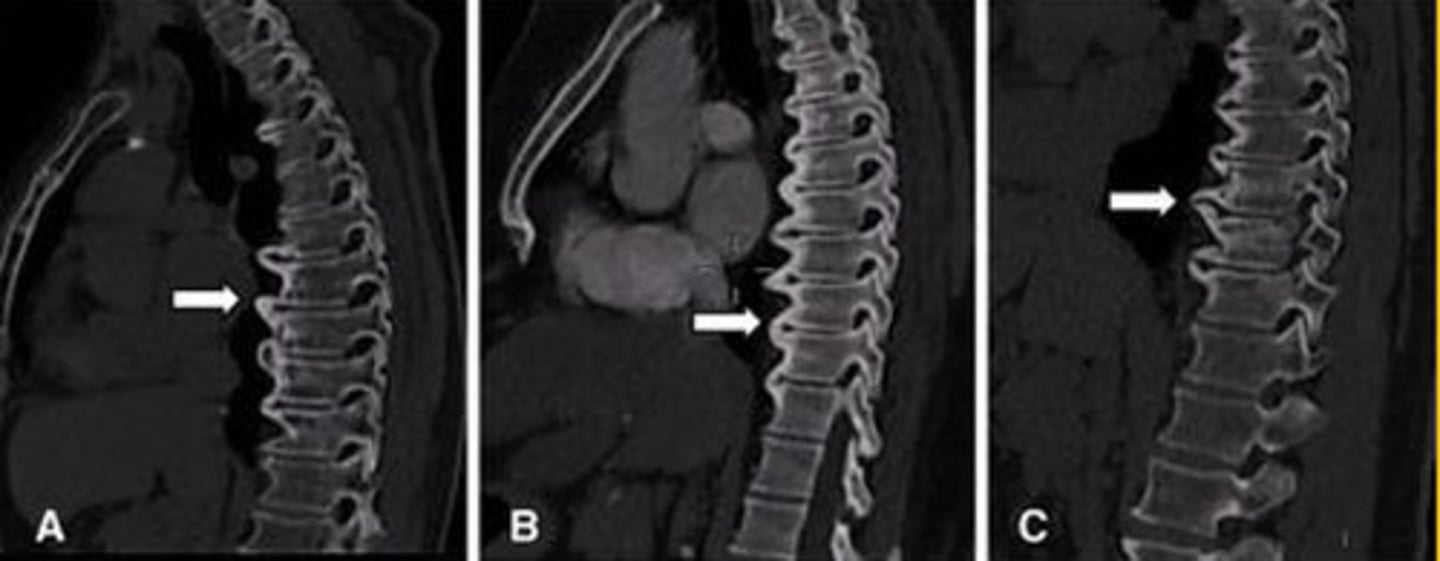

DISH

What is the blue arrow pointing at?

Sclerosis of the posterior vertebral line

What is the pink?

DISH (mid body to mid body)

What is in the red?

CT

What has the best image of cortical bone?

What is the arrow pointing at?

Mid body

Where does the ALL attach to the vertebrae?

DISH (mid body flow of the anterior vertebral line)

What is wrong with this image?